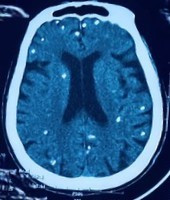

Người bệnh được chuyển lên từ tuyến trước vì rối loạn ý thức đe dọa suy hô hấp, hình ảnh cắt lớp vi tính sọ não và X-quang ngực cho thấy rất nhiều nốt cản quang trong nhu mô não và dưới da vùng ngực-bụng.

Nhiều nốt cản quang trong nhu mô não của người bệnh - Ảnh BVCC

Một vài u cục với kích thước tương ứng có thể sờ thấy dưới da vùng ngực và cánh tay của người bệnh.

Mặc dù xét nghiệm kháng thể IgM với sán dây lợn âm tính, các tổn thương trên X-quang gợi ý người bệnh trước đây bị nhiễm ấu trùng sán dây lợn, sau đó các nang sán trở nên vôi hóa và tồn tại lâu dài trong tổ chức. Người bệnh được điều trị theo phác đồ bệnh chính, đáp ứng và ra viện tiếp tục điều trị theo tuyến.

Nang sán dây lợn có thể tự thoái hóa hoặc bị vôi hóa, tạo nên nhiều hình ảnh cản quang phát hiện được trên phim X-quang như trường hợp bệnh nhân trên.